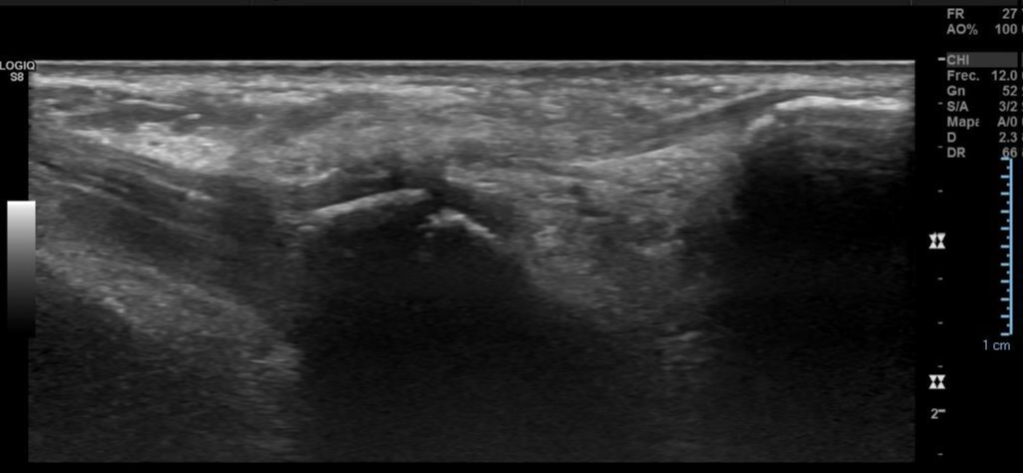

Imagen con aspecto de os peroneo de contornos corticales irregulares, con cambios inflamatorios de las partes blandas adyacentes, pudiendo estar en relación a fractura a este nivel.

Impresión diagnóstica: Imagen con aspecto de os peroneo de contornos corticales irregulares, con cambios inflamatorios de las partes blandas adyacentes, pudiendo estar en relación a fractura a este nivel. Se sugiere evaluar con radiografía.

Tendinosis del peroneo largo en su región distal.